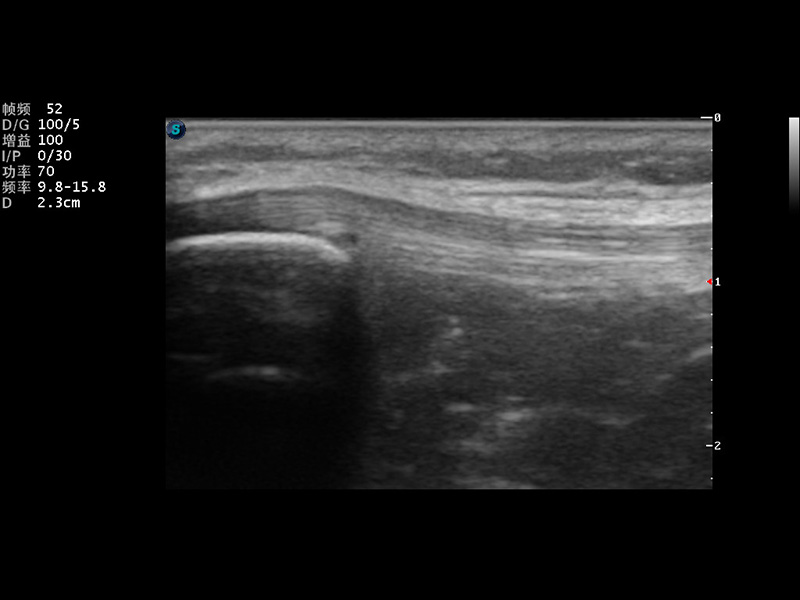

S9便携式彩色多普勒超声诊断仪是环球UG官网研发的高端便携彩超设备,外观设计新颖、产品性能卓越。S9在便携超声领域采用了突破传统的触摸屏交互设计,并以先进的软件硬件技术和设计理念,为您带来清晰的图像质量、稳定的工作性能和便捷的操作体验。

μ-Scan微米成像